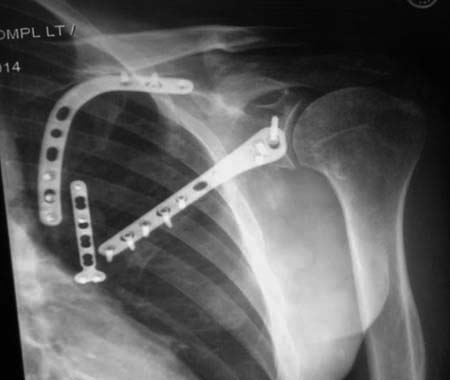

Здесь пример, стандартные снимки: плечо и лопатка прямой снимок, аксиллярный и косой снимки (Y-view) и фиксация пластинами по краям, где имеется более твердая кость. Специальные пластины, хотя любая 2.7 или 3.5 мм тубулярная пластина подойдут для фиксации перелома. Риск операции - это повреждение нерва во время доступа и ре-фиксация ротаторной манжетки если потребуется широкий доступ!